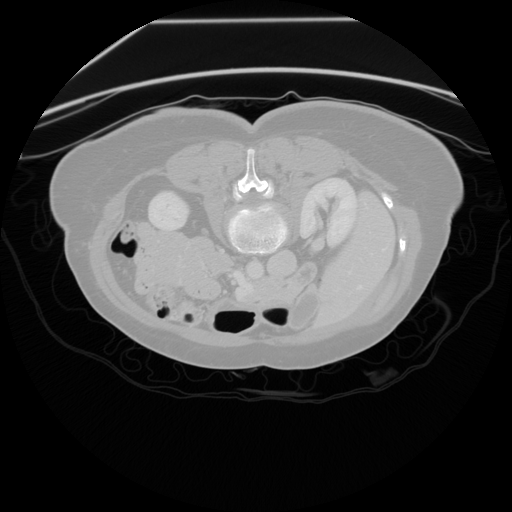

Figure 1: Example of moving (top) and fixed (bottom) image pairs. From left to right: brain MRI (T2w, T1w, T1Gd), abdomen CT from different subjects, retinal OCTA choroid, and retinal OCTA SCP scans

To address this problem, we propose a meta-learning-based registration meth-od that can efficiently use data from different domains. Specifically, we integrate an unsupervised learning-based registration model in a gradient-based meta-learning framework. The registration model is first trained using multiple registration datasets and then performs task-level learning using the multi-task data. The meta-learner finds an initialization point which can quickly adapt to various registration problems. After that, fine tuning is performed with the data of the target domain and applied to the test set. To demonstrate superiority, we trained the model for various 2D registration tasks from retinal Optical Coherence Tomography Angiography (OCTA) choroid, abdomen CT, and brain MRI scans and tested it on a registration of retinal OCTA Superficial Capillary Plexus (SCP) scans as shown in Fig. 1.

In our experiment, we used four datasets including retinal OCTA SCP, retinal OCTA choroid, abdomen CT, and Brain MRI. Both OCTA SCP and choroid datasets contained 368 moving and fixed image pairs collected from local university hospital, some of which were taken from same subjects at different times. The abdomen CT and brain MRI images were obtained from public Decathlon dataset [15]. Here, we define three tasks according to modality (T1w, T1Gd, and T2w) from the brain MRI dataset and two tasks in the abdomen CT dataset. Each 3D volume was divided in multiple axial slices and adjacent two slices were defined as a (M,F)𝑀𝐹(M,F) pair. All images were resized to a size of 400×400400400400\times 400 and histogram equalization was applied. Also, the range of intensity was rescaled to [0,1]. For training, we defined a set of five tasks as the source task set Tsource=subscript𝑇𝑠𝑜𝑢𝑟𝑐𝑒absentT_{source}= TbrainT1subscript𝑇𝑏𝑟𝑎𝑖𝑛𝑇1T_{brainT1}, TbrainT1Gdsubscript𝑇𝑏𝑟𝑎𝑖𝑛𝑇1𝐺𝑑T_{brainT1Gd}, TbrainT2subscript𝑇𝑏𝑟𝑎𝑖𝑛𝑇2T_{brainT2}, Tabdomensubscript𝑇𝑎𝑏𝑑𝑜𝑚𝑒𝑛T_{abdomen}, TChoroidsubscript𝑇𝐶𝑜𝑟𝑜𝑖𝑑T_{Choroid}. For evaluation, retinal OCTA SCP dataset was used as target domain data Dtargetsubscript𝐷𝑡𝑎𝑟𝑔𝑒𝑡D_{target}. It was divided into a fine-tuning set Tfinetunesubscript𝑇𝑓𝑖𝑛𝑒𝑡𝑢𝑛𝑒T_{fine-tune} (294 pairs) and a test set Ttestsubscript𝑇𝑡𝑒𝑠𝑡T_{test} (74 pairs). For evaluation, we manually labeled 20similar-to\sim30 bifurcation points on image pairs in Ttestsubscript𝑇𝑡𝑒𝑠𝑡T_{test}.